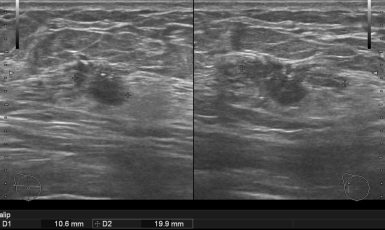

248번째 유방암 진단사례 (2019년3월27일) 양쪽 유방에 미세석회화 소견 및 다발성 결절들이 있어 수년전부터 다른 병원에서 지속적으로 정기 검사을 받으시다가 관악구 쪽..

247번째 유방암 진단사례 (2019년3월9일) 한달전에 다른 병원에서 시행한 공단 유방 촬영상 오른쪽 유방의 12시 방향에 결절 소견이 관찰되어 유방 초음파 검사 권유받..

246번째 유방암 진단사례 (2019년3월6일) 수개월전부터 오른쪽 가슴에 단단한 멍울이 만져졌으나 대수롭지 않게 생각하고 지내오시다가 가족이 발견한 후에 진료 권유받고 ..